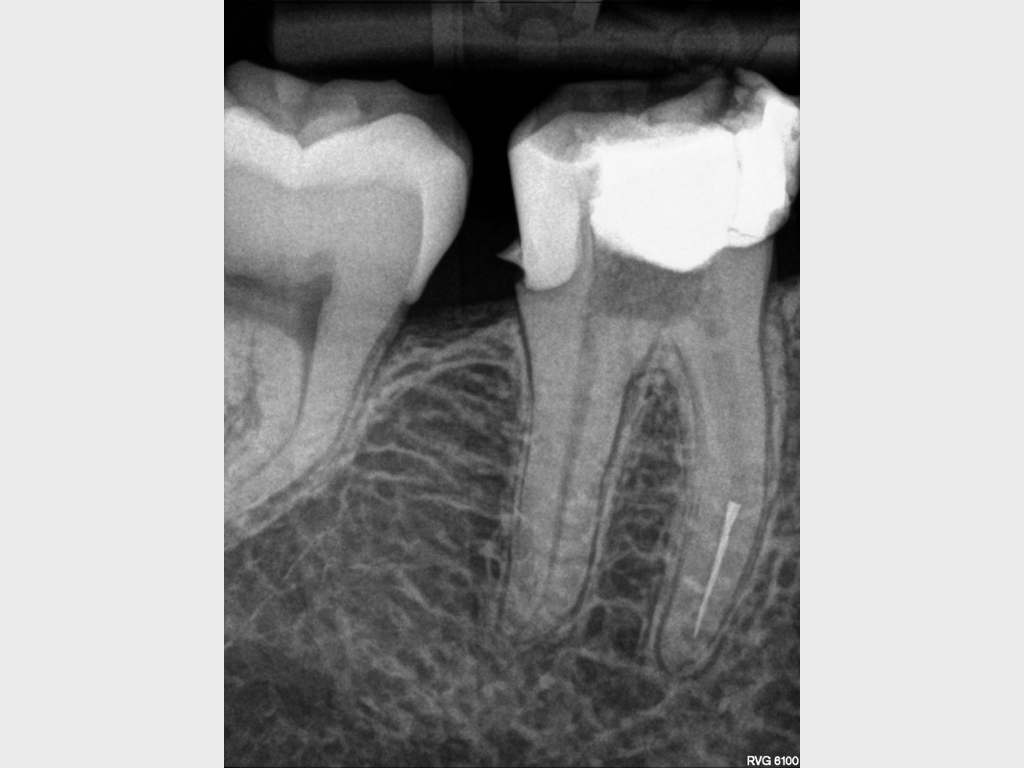

9653.001

1024 × 768

Anamnese